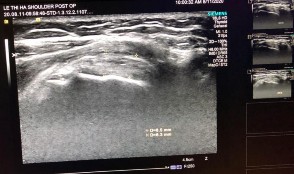

Hình phụ lục 1C: Kết quả khám lại sau mổ (Nguồn: BN nghiên cứu)

Hình phụ lục 1B: Kết quả liền gân trên siêu âm và sau mổ (Nguồn: BN nghiên cứu)